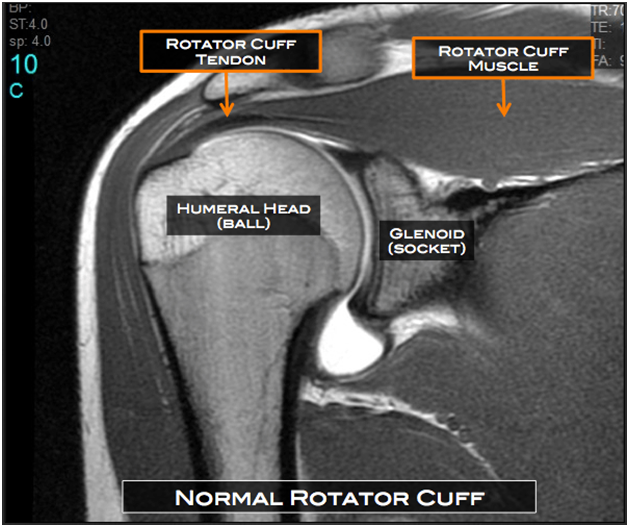

A rotator cuff tear is a common shoulder injury that occurs when one or more of the tendons in the rotator cuff get torn. The rotator cuff is a group of muscles and tendons that help move and stabilize the shoulder joint. This injury can cause pain, weakness, and difficulty in lifting the arm.